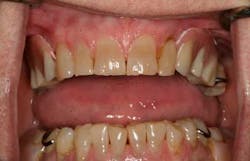

Light-body PVS impression material was injected around the posts to pick up soft-tissue detail (figure 4). After this, the RPD was picked up using an alginate impression (figure 5). I use Kromopan 100 (Kromopan USA, Inc.), which can be poured safely at the lab within a few days. The lab added teeth Nos. 5 and 11 as well as the Locator retentive nylons and their metal housings (figure 6). The modified RPD is well retained and esthetic (figure 7). The patient was so impressed with dental implants that she replaced her lower RPD with implant-supported crowns the following year.